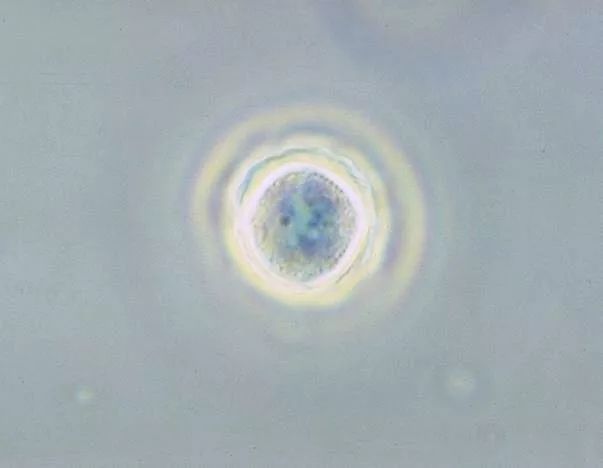

棘阿米巴原虫和耐格里阿米巴原虫同都划为阿米巴原虫目,是单细胞低等生物。

处在囊肿状态下的棘阿米巴原虫最经典的病例便是英国女子克莱尔长达十余年的折磨。